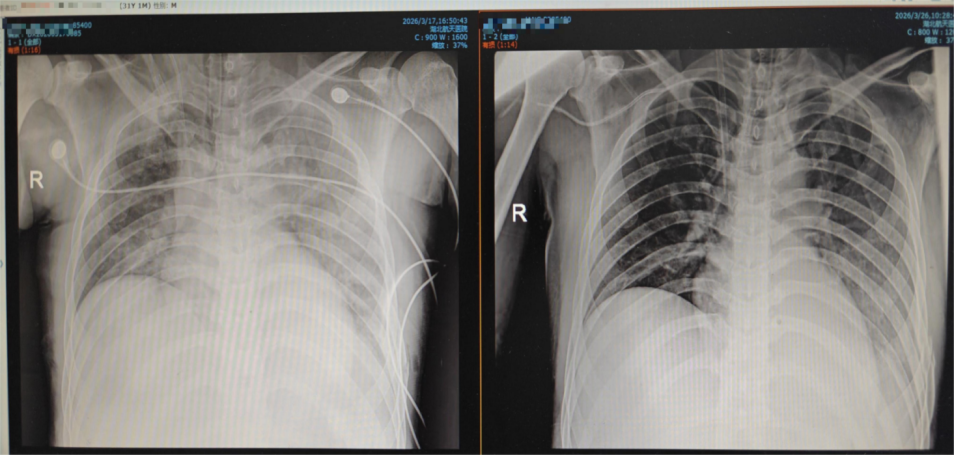

胸部DR對(duì)比:ECMO上機(jī)前和撒機(jī)前

3月17日下午,患者血氧飽和度再次驟降至78%,病情進(jìn)入生死臨界點(diǎn)。此時(shí),呼吸機(jī)已調(diào)至100%純氧、高PEEP模式,參數(shù)達(dá)到極限,床旁支氣管鏡檢查顯示氣道腫脹嚴(yán)重,患者雙肺持續(xù)“白化”,血?dú)夥治鲲@示氧合指數(shù)僅為64mmHg(正常人氧合指數(shù)需在300mmHg以上),生命垂危。

經(jīng)過16天的精準(zhǔn)救治與悉心守護(hù),患者病情持續(xù)好轉(zhuǎn):3月26日,ECMO撤機(jī)試驗(yàn)成功,患者氧合指數(shù)可維持在300mmHg以上,達(dá)到正常水平;3月27日,纖支鏡引導(dǎo)下經(jīng)皮氣管切開手術(shù)順利完成,出血量不足2ml;3月30日,患者神志完全轉(zhuǎn)清,肢體活動(dòng)正常,可遵囑完成簡單動(dòng)作;3月31日,患者成功脫離呼吸機(jī),生命體征平穩(wěn),這場長達(dá)16天的生死救援圓滿取得勝利。